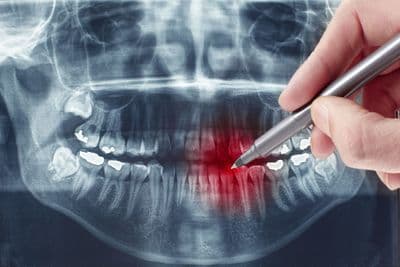

La conservativa è una branca della medicina che si occupa delle patologie che colpiscono l’apparato stomatognatico: denti, gengive, mascellari, articolazioni temporo-mandibolari, ghiandole salivari, tessuti neuro-muscolari e mucose orali.

In particolare, la conservativa tratta lesioni dello smalto e dei denti dovute principalmente a carie o traumi, in modo da rispristinarne la normale funzione e l’estetica.

L’endodonzia si occupa della prevenzione, della diagnosi e della cura delle lesioni dell’endodonto, ovvero della polpa dentaria. |

La terapia endodontica, più comunemente conosciuta con il termine “devitalizzazione”, si attua quando una lesione cariosa o traumatica altera in modo irreversibile il tessuto pulpare.